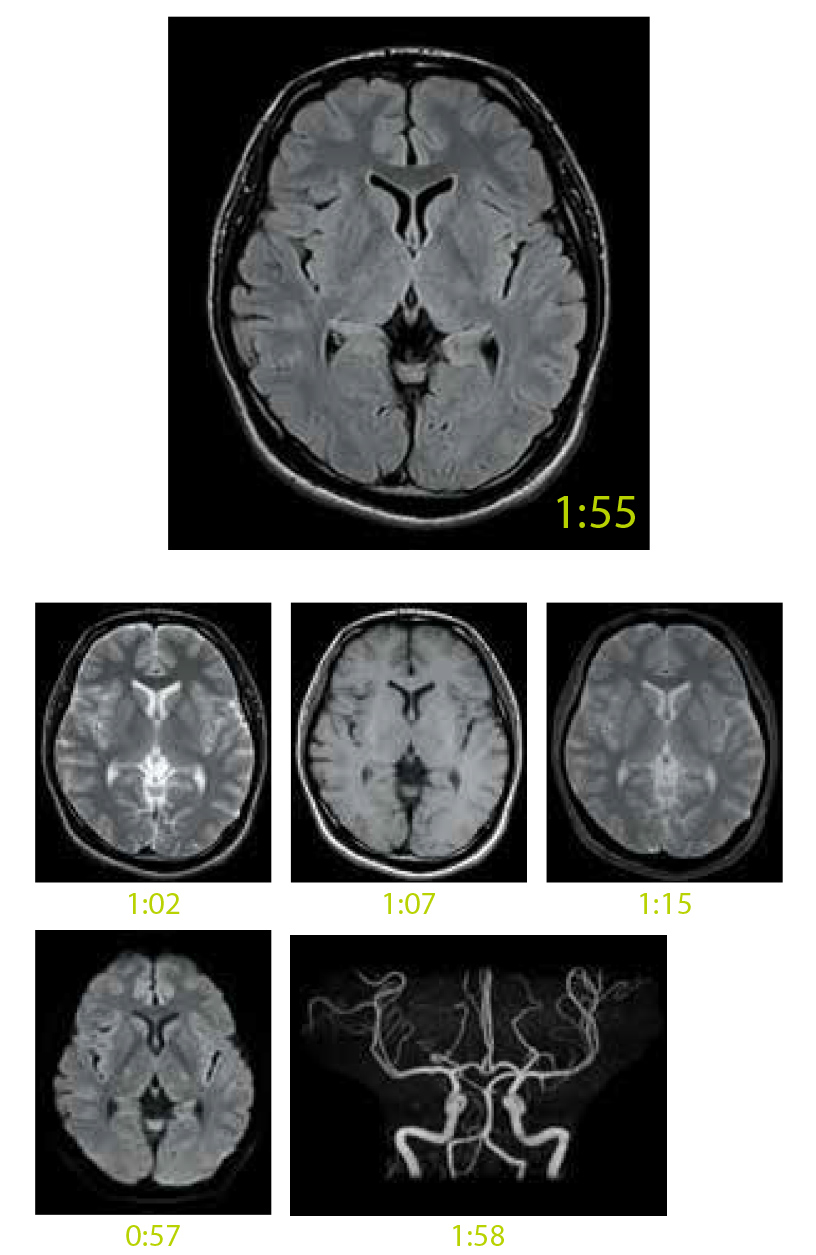

IP-RAPID is high-speed imaging using iterative processing, reducing scan times by up to 60% while maintaining image quality comparable to conventional imaging methods that don't apply IP-RAPID.

IP-RAPID is a technology that can reduce scan time while maintaining image quality.

By combining undersampling and iterative reconstruction, it can be combined with various regions and functions.

SNR and spatial resolution can also be improved while maintaining the scan time.

Value is compared between the following examples